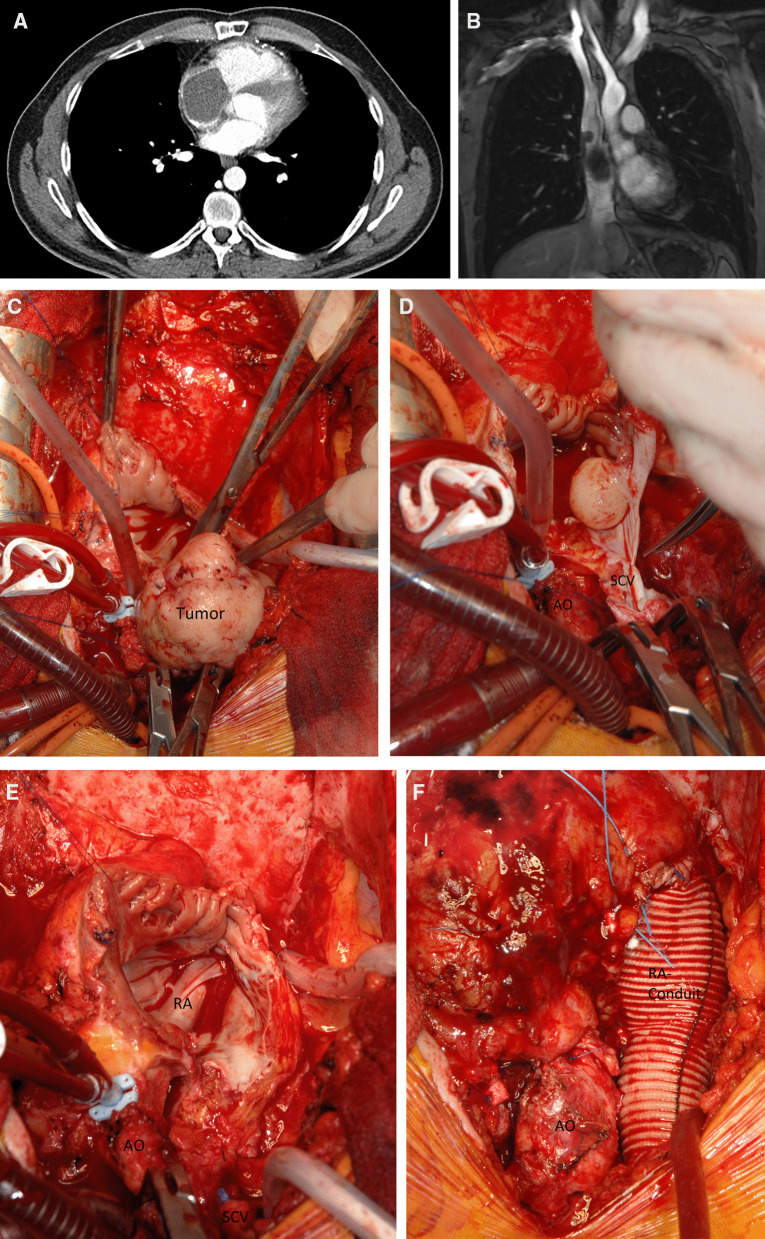

Fig. 1.

A CT shows a large RA tumor mass with subtotal obliteration of the tricuspid valve with a major portion prolapsing into the RV. B Cardiac MR angiography shows a large RA tumor mass emerging from the lateral wall of the SCV with subtotal obliteration of the RA. C–E Intraoperative view during complete resection of a RA tumor. F Intraoperative view after complete resection of a RA tumor and reconstruction with a tailored Dacron prosthesis

A 23-year-old man was referred to our department when transthoracic echocardiography (TTE) suggested a right atrial (RA) tumor. Emergency computed tomography (CT) revealed complete RA obstruction and tumor prolapse into the right ventricle (RV) (Fig. 1A), causing inflow congestion, pleural and minimal pericardial effusion. The patient, in cardiogenic shock, was immediately transferred to surgery. On moderately hypothermic non-beating heart bypass with snared caval veins, the firm tumor (8 × 5 × 5 cm, pedicle diameter 2.5 cm), adherent to the lateral RA wall, was macroscopically completely resected. The defect was closed with pericardial patch plasty. The NOS.G-3 spindle-cell sarcoma contained mitotic cells. Immunohistochemistry reacted positively with cytokeratin 7 and 19, EMA antibody. The proliferative ratio, evaluated with MIB1 (Ki-67), reached up to 60% of the cells. Fast-track extubation and perioperative course were uneventful. The patient was discharged with sinus rhythm and 65% ejection fraction (EF). Magnetic resonance (MR) imaging and positron emission tomography (PET) showed no metastases. Two cycles of radiotherapy (single dose of 1.8 Gy in the tumor region, with a tumor dose up to 50.4 Gy) were ordered when the final histology showed a few tumor cells near the resection margin.

At 21 months postoperatively, CT and cardiac MR angiography showed a tumor emerging from the lateral wall of the superior caval vein (SCV) and the RA (4.4 × 5.3 × 5.8 cm) (Fig. 1B). After careful resternotomy using an oscillating saw, meticulous preparation of massive adhesions after irradiation was performed. Moderately hypothermic non-beating heart bypass via the brachiocephalic vein and the right femoral vein was started. Both caval veins were snared. The ascending aorta was clamped, and 1000 ml of blood cardioplegia was applied. After incision of the right atrium, waste suction was used. The tumor, adherent to the wall of the superior caval vein, was resected in toto with the vessel wall to achieve clear margins. The complete free wall of the RA with the adherent tumor, the RA appendage, and the pericardial patch of the first operation were excised (Fig. 1C–E). After the cardiac tumor was completely resected, the wall defect was replaced with a tailored Dacron tunnel prosthesis from the superior caval vein sleeve to the inferior caval vein and the free wall of the RA (Fig. 1F). Histology confirmed R0 resection of a G-3 spindle-cell sarcoma. Tumor cells had 25 mitoses per 10 high power fields; distinct tissue necrosis was present. Immunohistochemistry was identical to the first tumor and S100 positive. Reverse transcription-polymerase chain reaction (RT-PCR) confirmed SYT/SSX1(t(X;18)(p11.2;q11.2)SYT/SSX) consistent with the specific diagnosis of a monophasic fibrous synovial sarcoma. TTE upon discharge showed normal biventricular function with EF 65%. The heart was tumor-free upon PET-CT 24 months thereafter. A sudden progression with innumerable pulmonary nodules caused only minimal exertional dyspnea, and the patient received monthly cycles of palliative monochemotherapy with ifosfamide, which he tolerated well. Thirty months after the first operation, he developed left-sided hemiparesis and succumbed to hemorrhage from a brain metastasis.